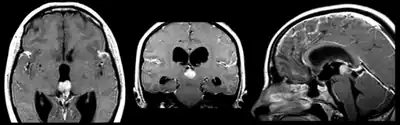

| Pineoblastoma localized predominantly in posterior part of the third ventricle | |